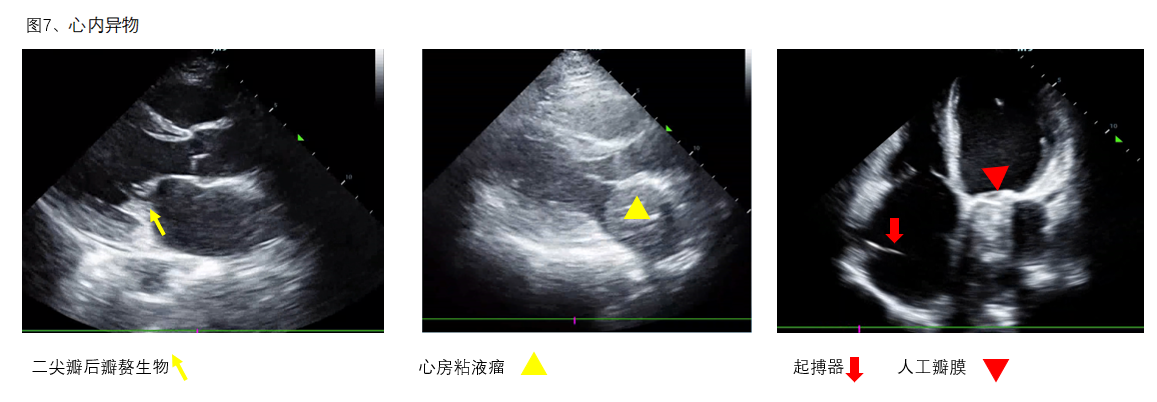

F、异物观察心腔内、瓣膜上有无异物(图7),可协助明确病因并指导进一步治疗。

(图7)